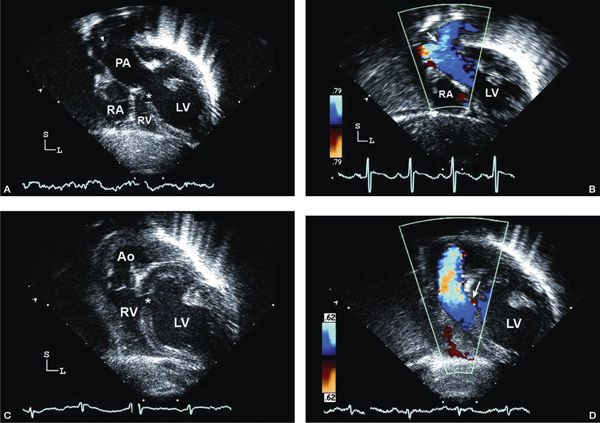

Subcostal four-chamber (coronal) view Subcostal examination begins with a determination of abdominal viscera and atrial situs in all patients. Subcostal four-chamber (coronal) views will show dilation of the RA with absence of the connection to the RV (Fig. 12.2A [Video 12.1A]). As foreshortening of the RV may occur in this plane, short-axis (sagittal) plane imaging is useful for “three-dimensional” assessment of right ventricular size. The atrial septum is best visualized from subcostal imaging planes, and characterization of the ASD should be performed. Prominent Eustachian valve tissue may be present but typically does not contribute to obstruction. Color Doppler will show a right-to-left shunt from the RA to the left atrium (LA) and no flow from the RA to the RV. It is unusual for the ASD to be restrictive, but pulsed-wave Doppler interrogation should be used to evaluate the RA-to-LA gradient, tracing the signal over three cardiac cycles to determine a mean gradient. An atrial shunt is obligatory for survival; therefore, a restrictive ASD may result in severe hemodynamic compromise requiring urgent septostomy. Evaluation of the great arteries from multiple imaging planes to determine ventriculoarterial connections is important (Fig. 12.2B–C [Video 12.1B, C]). An enlarged, posterior great artery (PA) that bifurcates early is consistent with transposed great arteries (ventriculoarterial discordance) (Fig. 12.3A–B [Video 12.2A]). Examination of the ventricular septum may provide information on the size and location of the VSD, but orthogonal views will be needed. In tricuspid atresia, the VSD is usually muscular; rarely, the VSD can be doubly committed and subarterial or outlet in nature. The mitral valve and left ventricular function can be assessed initially from the four-chamber subcostal plane.

Subcostal short-axis (sagittal) view Subcostal short-axis views demonstrate the absent connection between the floor of the RA and the hypoplastic RV. Orthogonal views are very useful for evaluation of the atrial septal anatomy. Again, the right-to-left shunt should be unrestricted in the setting of an adequate interatrial communication. Rightward angulation of the transducer facilitates evaluation of the absent communication between the RA and the hypoplastic RV, and the size of the RV is more easily assessed in the subcostal short-axis view than in the four-chamber imaging plane (Figs. 12.2C and 3C–D). Evaluation of the size of the VSD between the LV and hypoplastic anterior RV is important for documenting sites of obstruction to arterial outflow. Careful sweeps from right to left are important to obtain complete information about the location and degree of right ventricular outflow obstruction. Assessment of the ventriculoarterial connection is performed from the short-axis view; again, the proximal bifurcation of the PA should be assessed. The presence of parallel great arteries suggests transposition (ventriculoarterial discordance). A small anterior aorta should prompt a careful evaluation for coarctation of the aorta from additional views.

Figure 12.3. Tricuspid atresia with transposed great arteries; subcostal long-axis (coronal) views. A: Dilated left ventricle (LV), hypoplastic right ventricle (RV), and a small muscular ventricular septal defect (asterisk). Note the pulmonary artery (PA) arising from the LV with early bifurcation (arrowhead). B: Color Doppler imaging in the same patient demonstrating flow in the PA bifurcation (arrow). C: Slight anterior angulation of the transducer demonstrates the LV, hypoplastic RV, and the restrictive ventricular septal defect (asterisk). The anterior aorta (Ao) arises from the hypoplastic RV. D: Color Doppler demonstrating the flow across the small ventricular septal defect (arrow), antegrade into the aorta (Video 12.2).